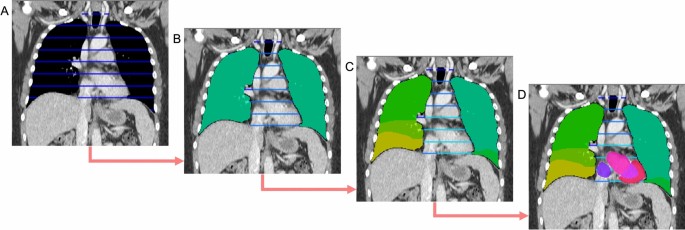

This study used a selection of datasets available on The Cancer Imaging Archive (TCIA)10 to train and evaluate the SALT approach. For the training, 750 CT scans from the Sparsely Annotated Region and Organ Segmentation (SAROS)11 dataset were used (600 for training and 150 for validation). In this dataset, the segmentations target anatomical landmarks that are relevant for body composition analysis (BCA)5,12. The annotations cover a wide range of areas such as the abdominal and thoracic cavities, bones, brain, mediastinum, muscles, pericardium, spinal cord, and subcutaneous tissue. In addition to these annotations, segmentations of organs, vessels, and specific muscles and bones were generated using Version 1 of the TotalSegmentator models2,13 for the same dataset of 750 scans. The TotalSegmentator predictions were then fused with the SAROS annotations to create a single dataset of 750 scans containing all labels. For SAROS, smaller labels such as the thyroid, submandibular, and parotid glands were not included in the final segmentation. This exclusion was not due to any limitation of the SALT method but rather because these labels were sparsely represented in SAROS and more consistently available from TotalSegmentator, which already provides high-quality gland segmentations. Thus, the merged dataset prioritizes label consistency and coverage across larger and smaller anatomical structures. This fusion is illustrated in Fig. 1, which highlights the natural tree-like organization of the human body. For example, the body encompasses the thoracic cavity, which itself includes organs like the lungs and heart. These organs, in turn, can be subdivided further into more specific segments, such as the lobes of the lungs and the atria and ventricles of the heart.

Example of a hierarchical segmentation. (A) In the thorax, the biggest region is the thoracic cavity. (B) The thoracic cavity can then be subdivided into lungs and mediastinum. (C) The mediastinum has a further subregion the pericardium, and the lungs can be subdivided into lower/middle/upper left/right lobes. (D) The pericardium contains the heart, which can be subdivided into myocardium and left/right ventricle/atrium. The full segmentations originate from the TotalSegmentator, while the sparse segmentations are from SAROS.